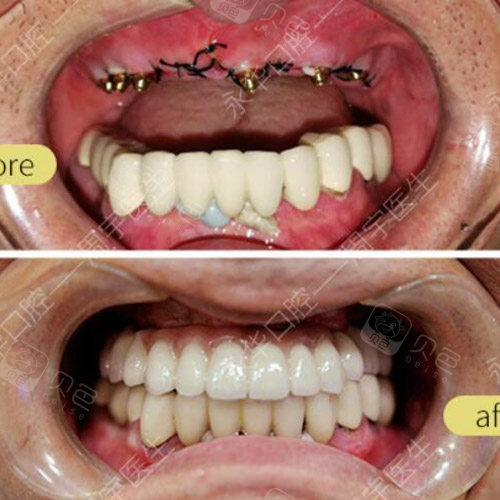

种植牙手术对比案例

种植牙前后对比案例